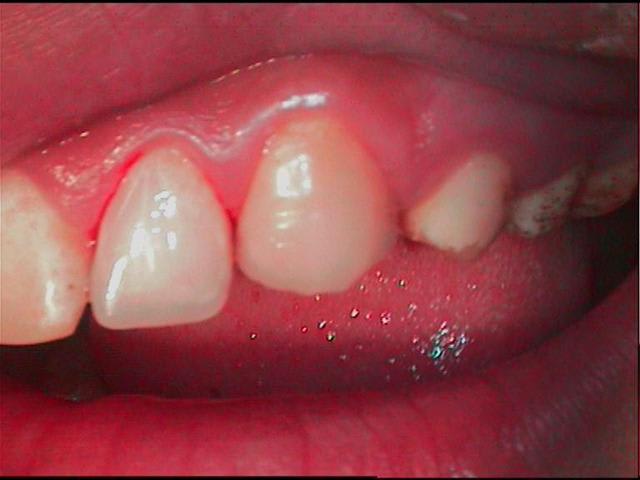

tiens! pendant que je suis en pedo, et que mac est occupé ailleurs, la suite, donc en definitive, glumla et flow,pas de taille,pas d'etching,pas de sensibilité post op, je crains pour les faces occl des post, sinon ça filoche pas trop mal pour l'instant...

1 sceu5w - Eugenol

1bis gqoz5j - Eugenol